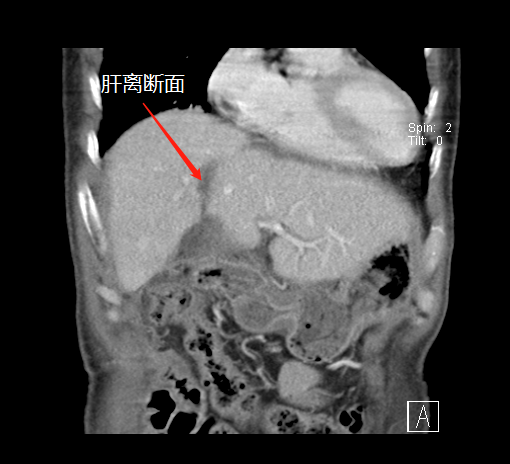

術(shù)前,左肝體積很小

第一次術(shù)后,結(jié)扎門靜脈劈開肝臟

左肝增生,第二次手術(shù)切除腫瘤

第一次手術(shù)后

經(jīng)過20天左右的“養(yǎng)肝”,經(jīng)CT復(fù)查顯示,患者的左側(cè)肝臟體積已增長至42.8%,這時候,也就達(dá)到了我們說的“養(yǎng)大好肝、再切病肝”,因為此時好肝已經(jīng)足以維持患者身體的運(yùn)轉(zhuǎn)需要。